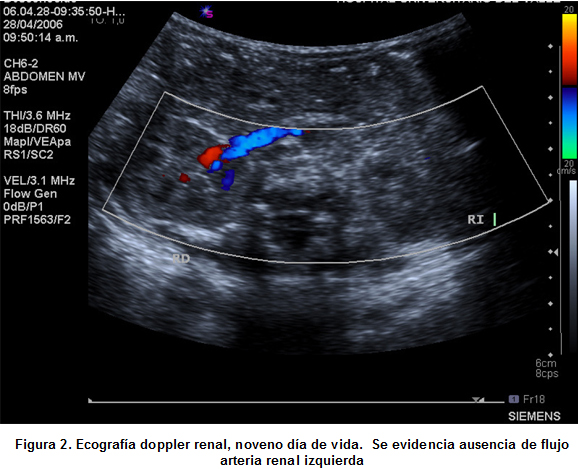

Se hospitalizó en la Unidad de Recién Nacidos (CIRENA) del Hospital Universitario del Valle (HUV), un recién nacido de género másculino, pretérmino de 34 semanas, con peso 2,035 g, con signos de dificultad respiratoria por lo que se realizó cateterismo umbilical venoso y arterial. Al cuarto día de vida presenta cifras tensionales elevadas y al séptimo día se evidencia acrocianosis, ausencia de pulsos y no detección de tensión arterial en miembros inferiores. Al octavo día de vida se retiran catéteres umbilicales, persiste hipertenso y con cambios descritos en miembros inferiores. Se realiza ecocardiograma observado trombo a nivel de arteria aorta. En su noveno día de vida se confirmó el diagnóstico por medio de ecografia Doppler (Figuras 1 y 2) donde se evidenció trombo que compromete parcialmente la arteria aorta y totalmente la arteria renal izquierda sin observarse flujo sanguíneo en riñón izquierdo.